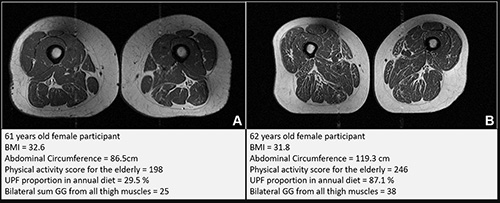

Figure 2. Representative axial T1-weighted spin-echo thigh MRI scans in (A) a 61-year-old female participant and (B) a 62-year-old female participant. Both participants were of similar age and body mass index (BMI, calculated as weight in kilograms divided by height in meters squared). Both had Physical Activity Scale for the Elderly scores above the mean score in the study. According to the World Health Organization definition, the participant in B qualified as having abdominal obesity (abdominal circumference ≥ 88 cm). Abdominal circumference is a measure of central obesity that captures fat distribution and serves as an indicator of cardiometabolic health. Compared with the participant in A, the participant in B had a higher proportion of ultra-processed food (UPF) in their diet (87.1% vs 29.5%) and exhibited fattier thigh muscles bilaterally, with Goutallier grade (GG) for all thigh muscles summing to 25 for the participant in A and 38 for the participant in B.